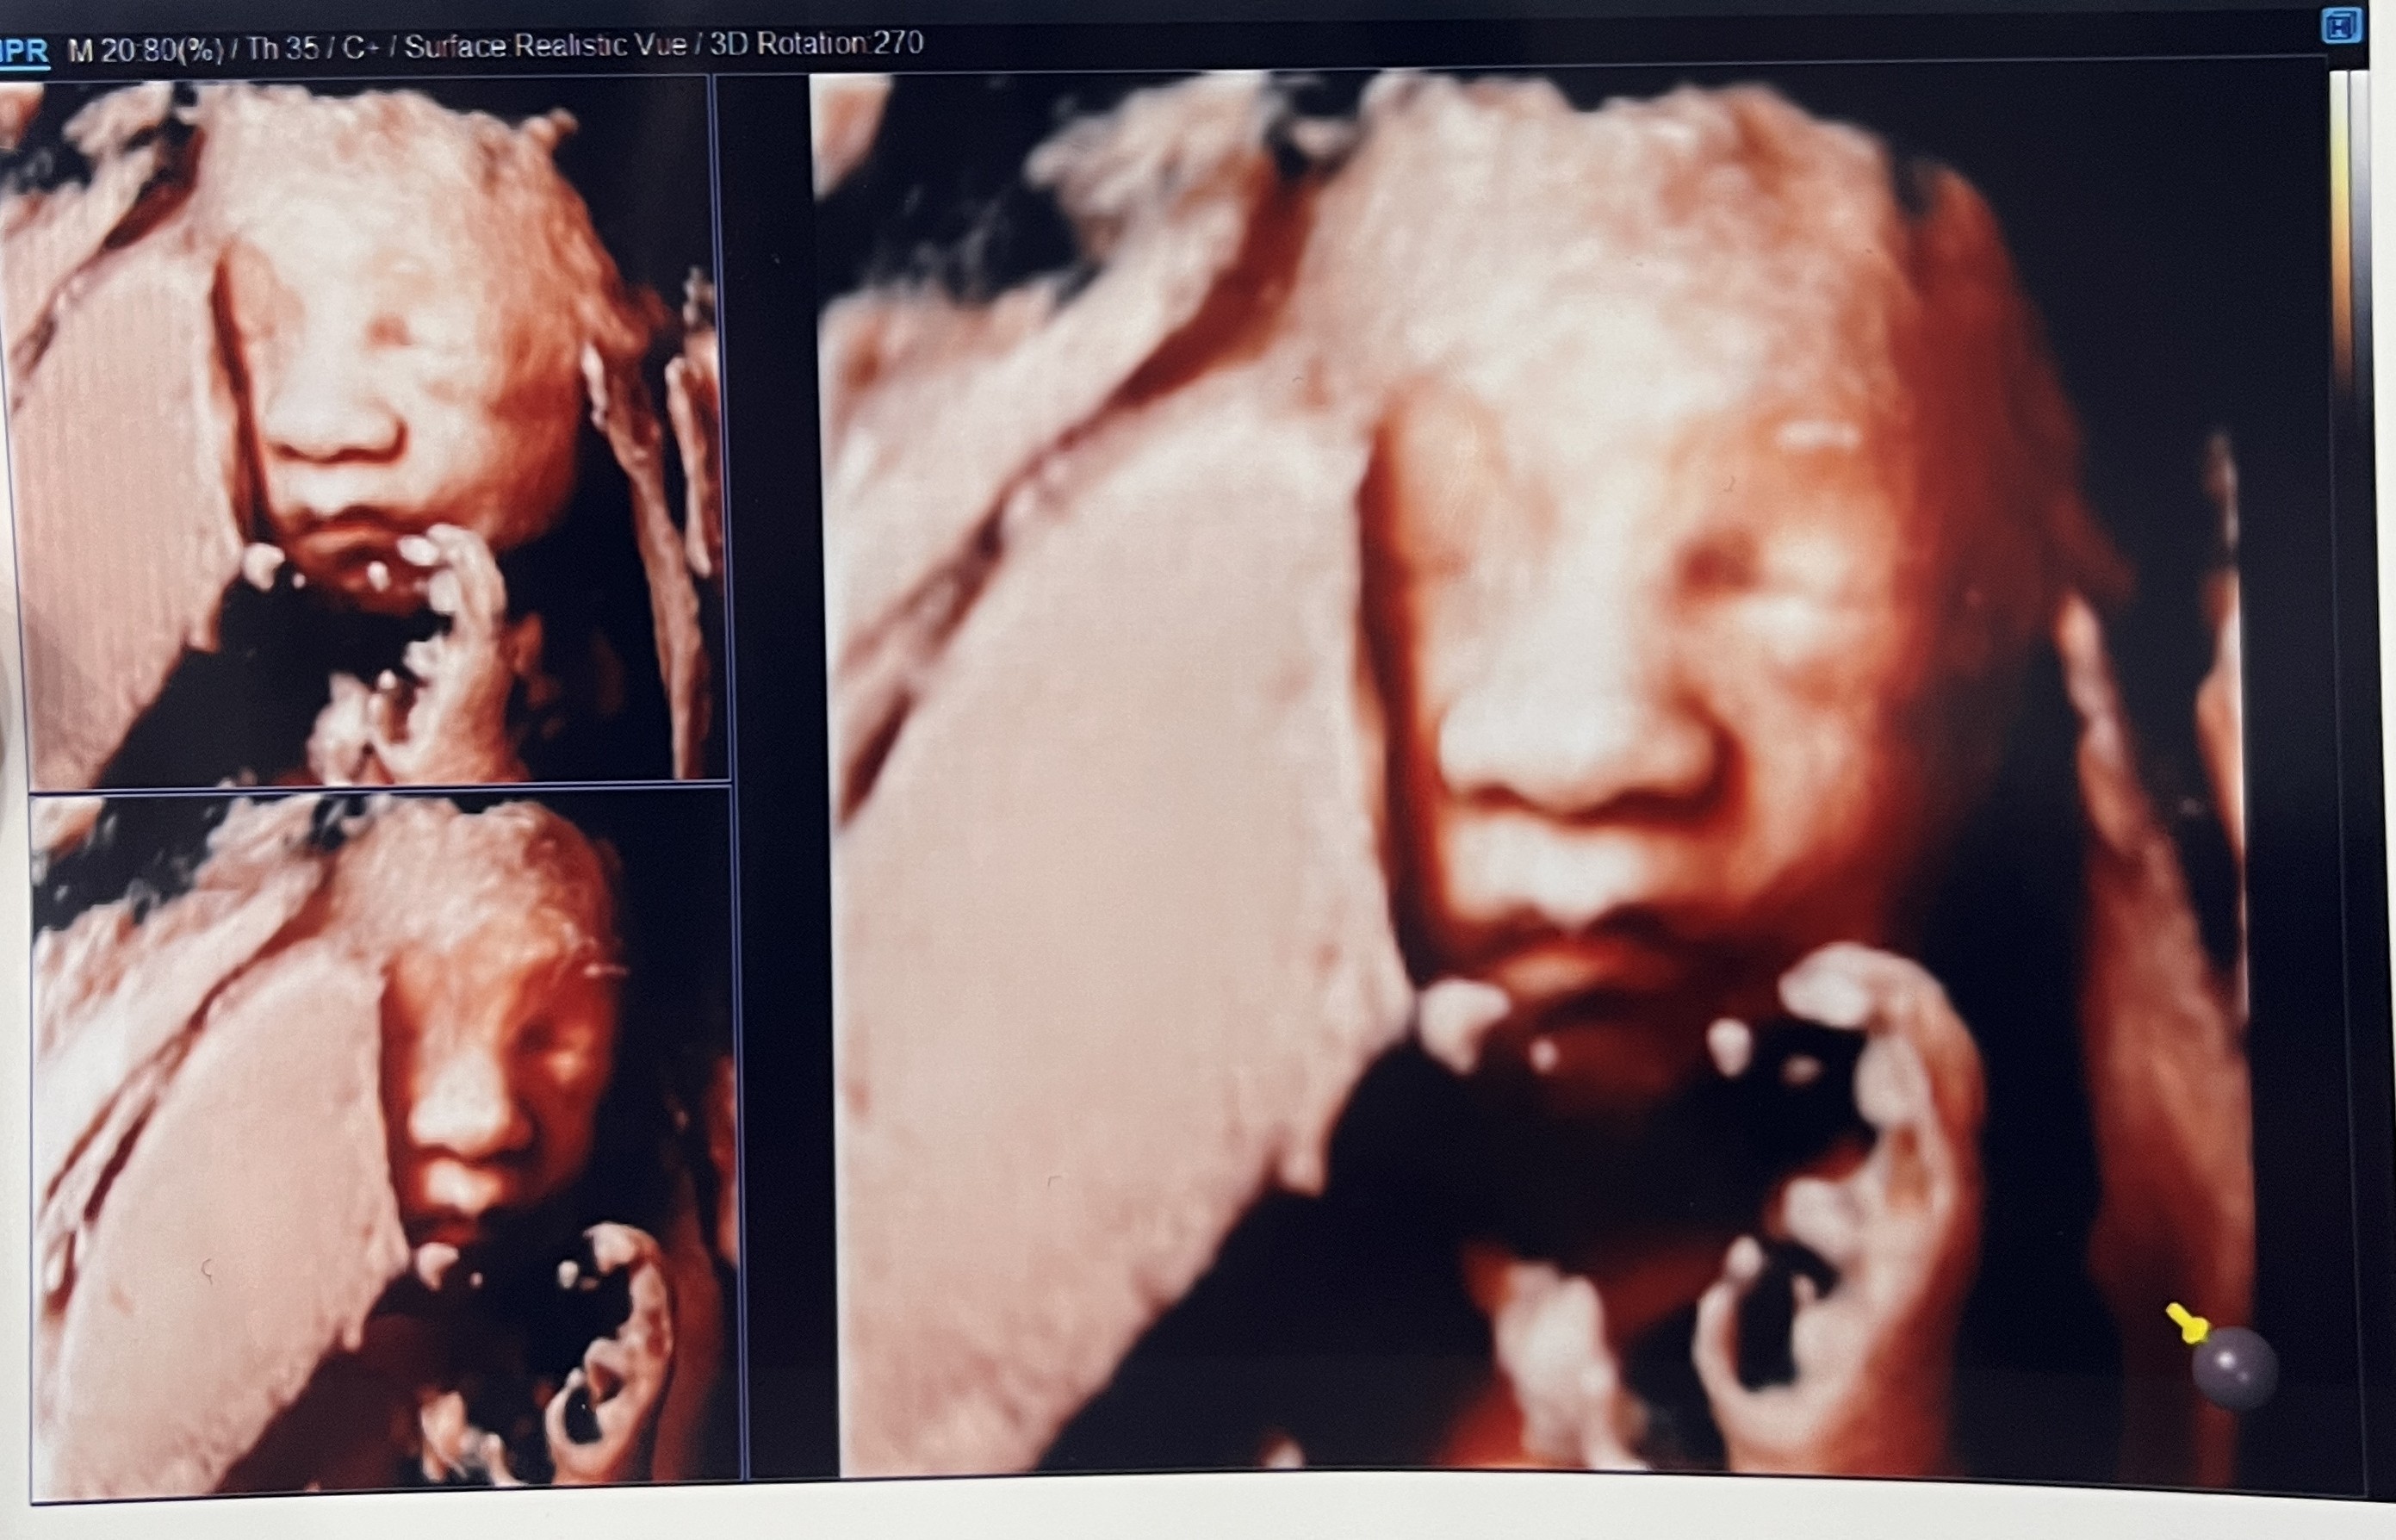

퐁팡아~!!!>_<

입체 초음파는 꼭 이곳에서 찍으셨으면 좋겠다.. 가격도 다른 병원들에 비해 아주 좋고, 직원 분들도 친절하고,

의사 선생님이 진짜 열심히 입초 잘 나오게 찍어주시려고 애써주셨다.

처음에 입초 찍으려고 보는데, 퐁팡이가 너무 얼굴을 안보여줘서 초코우유 먹고 다시 오라고 하셔가지고

버거킹 가서 아이스 초코 원샷하고 조금 걷다가 다시 들어갔당 :)

의사 선생님이 "어우 코가 크네. 남편 분이 코가 크신가봐요. 코 크다!" 라며 계속 강조하시는데 진짜 크다ㅋㅋㅎㅋㅎㅎㅋㅎ

외할아버지 닮았니~!?!?